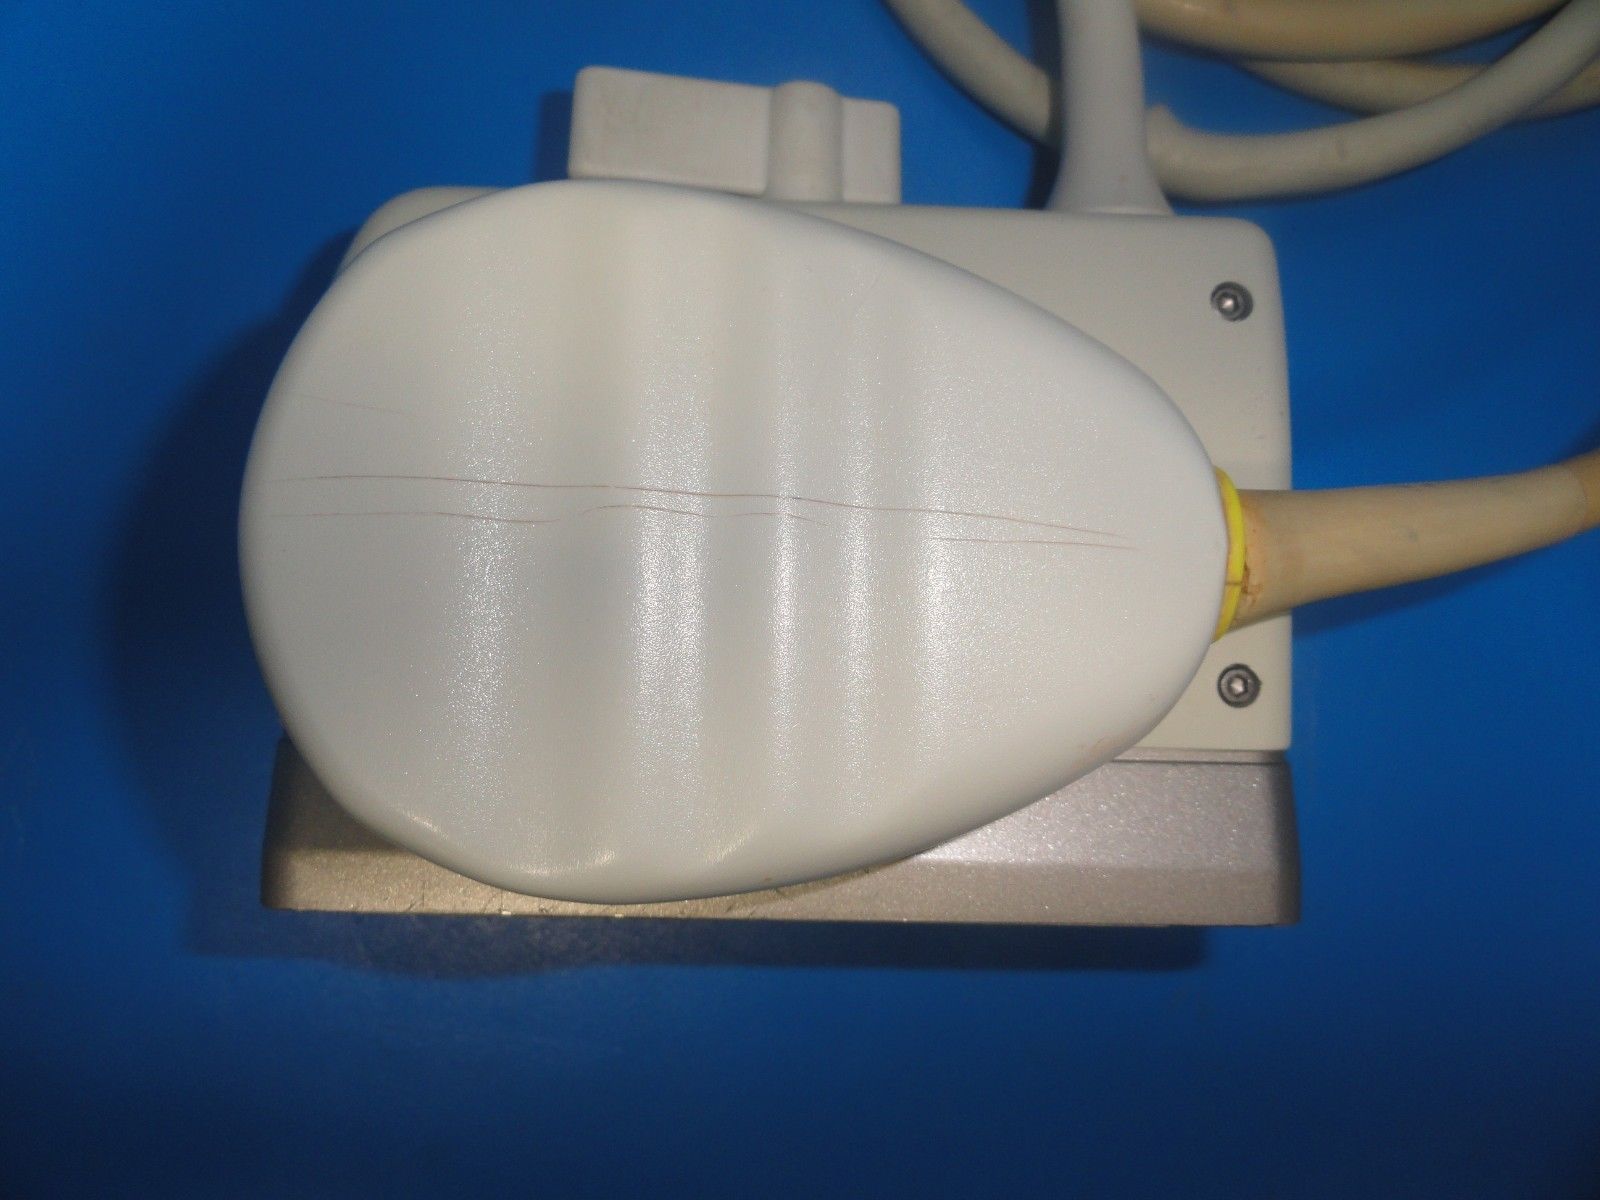

The ATL HDI C4-2 40R Curved Array Broadband Probe (6322) is a versatile ultrasound transducer designed for abdominal and OB/GYN imaging. Featuring a 4-2 MHz frequency range, this curved array probe provides excellent image clarity and depth penetration, making it ideal for imaging both superficial and deeper structures. It is particularly effective for abdominal, obstetric, and gynecological examinations, allowing healthcare professionals to capture clear images of the uterus, ovaries, and other abdominal organs. The broadband capabilities of the C4-2 40R ensure high-resolution images across a wide range of patient types and conditions, while its ergonomic design enhances comfort and ease of use during extended procedures. Compatible with the ATL HDI ultrasound systems, this probe offers seamless integration and optimal performance, helping clinicians make accurate and timely diagnoses. Whether for routine checks or more specialized exams, the ATL HDI C4-2 40R is a reliable, high-performance tool for medical imaging.